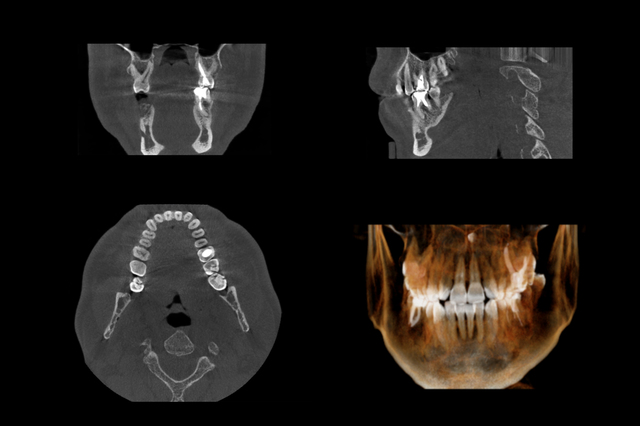

Set of MRI scanner slices of dental part of adult human male scull with multiple problems on white background.

すべての歯並び・咬み合わせの不正がマウスピースで改善できるわけではありません。適応の見極めが重要です。

- 重度の不正咬合、骨格性のズレ、顎変形、歯を大きく移動させる必要のある場合などは、マウスピースだと困難なケースがあります。

- 初期カウンセリングで、シミュレーション、模型、CT・レントゲン(セファロ撮影など)を用いて、詳細な検査・診断を行う医院を選ぶことをお勧めします。経験が浅い医院では、セファロを撮らず進めてしまう例も指摘されています。